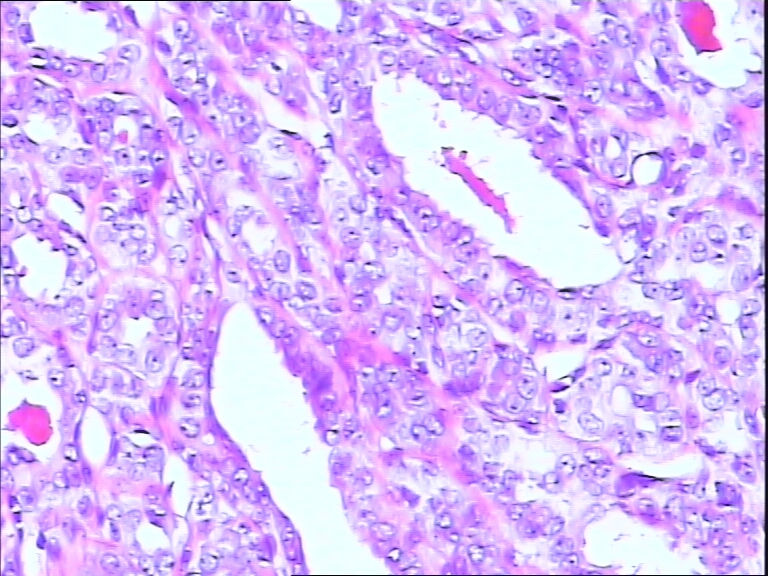

42y

左乳头有3mm结节

灰白不整形组织一块:0.7*0.5*0.4

导管内乳头状肿瘤